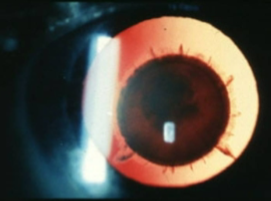

persistent hyperplastic primary vitreous (aka persistent fetal vasculature)

hyperplasia of tunica vasculosa lentis

unilateral

decreased VA

secondary PSC

strabismus

microphthalmos

leukocoria

PHPV/PFV

PHPV